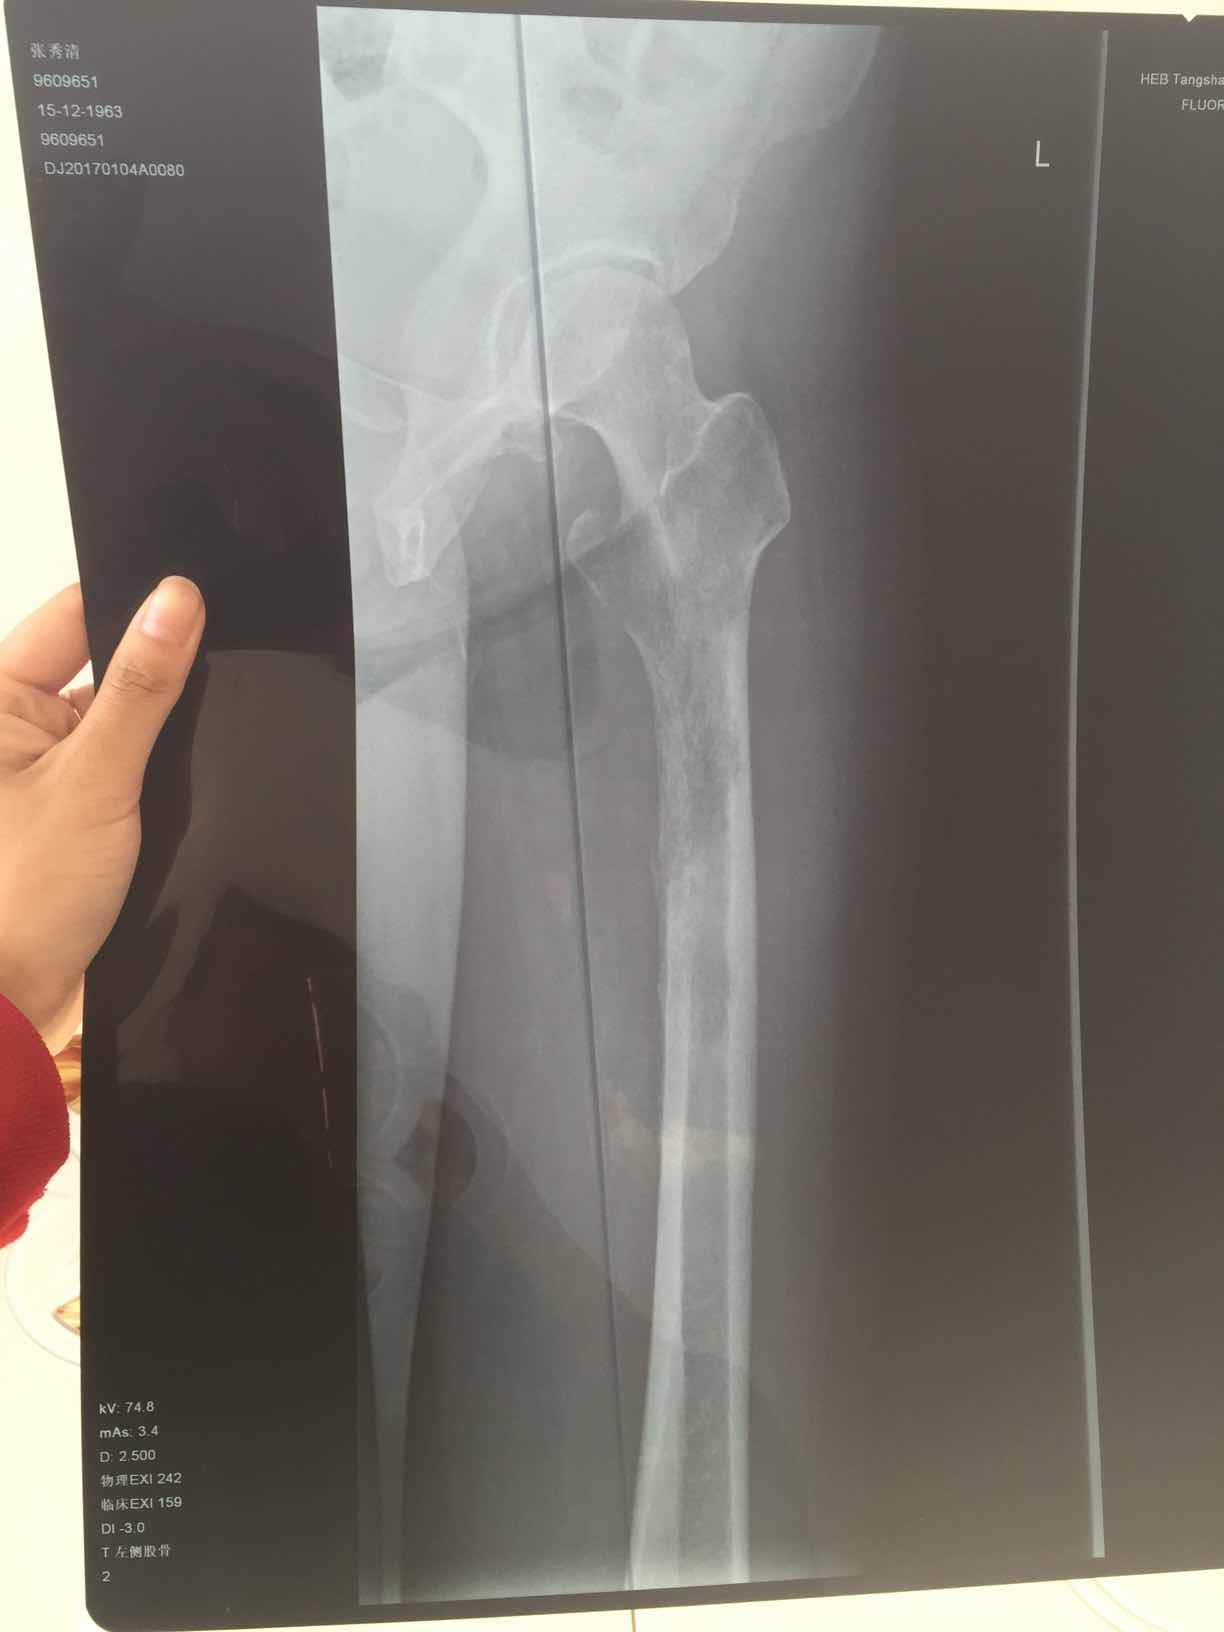

妈妈肺腺癌晚期骨转严重大腿根骨裂求大家帮忙

妈妈年前左大腿总疼,去医院检查说是腰间盘突出,在家卧床躺了3个月,前两个月还好,后一个月疼痛难忍。再去检查才发现是肺癌转移,然后主要转移到腿部比较严重,大腿根在不知情的情况下还掰了一下,造成了骨裂。去医院检查,骨科医院说是腿能做手术,但是还是建议先控制肿瘤,去了肿瘤医院,肿瘤医院说是腿没办法治疗了,因为妈妈大腿掰了一下已经目前卧床影响行走了,1月4号确诊,半月后开始打了骨转针,和吃了靶向药易瑞沙,我家是19突变,在这之前腿疼痛难忍,吃了易瑞沙就不疼了,但是还是由于大腿根骨裂影响行走,目前妈妈食欲还不错,睡眠也还好,就是躺着总说很累,求大家帮帮我,有懂ct这方面的也可以帮我看看,妈妈的腿能不能自愈,毕竟没有骨折。钙片骨转针一直在吃。求求大家帮帮忙。